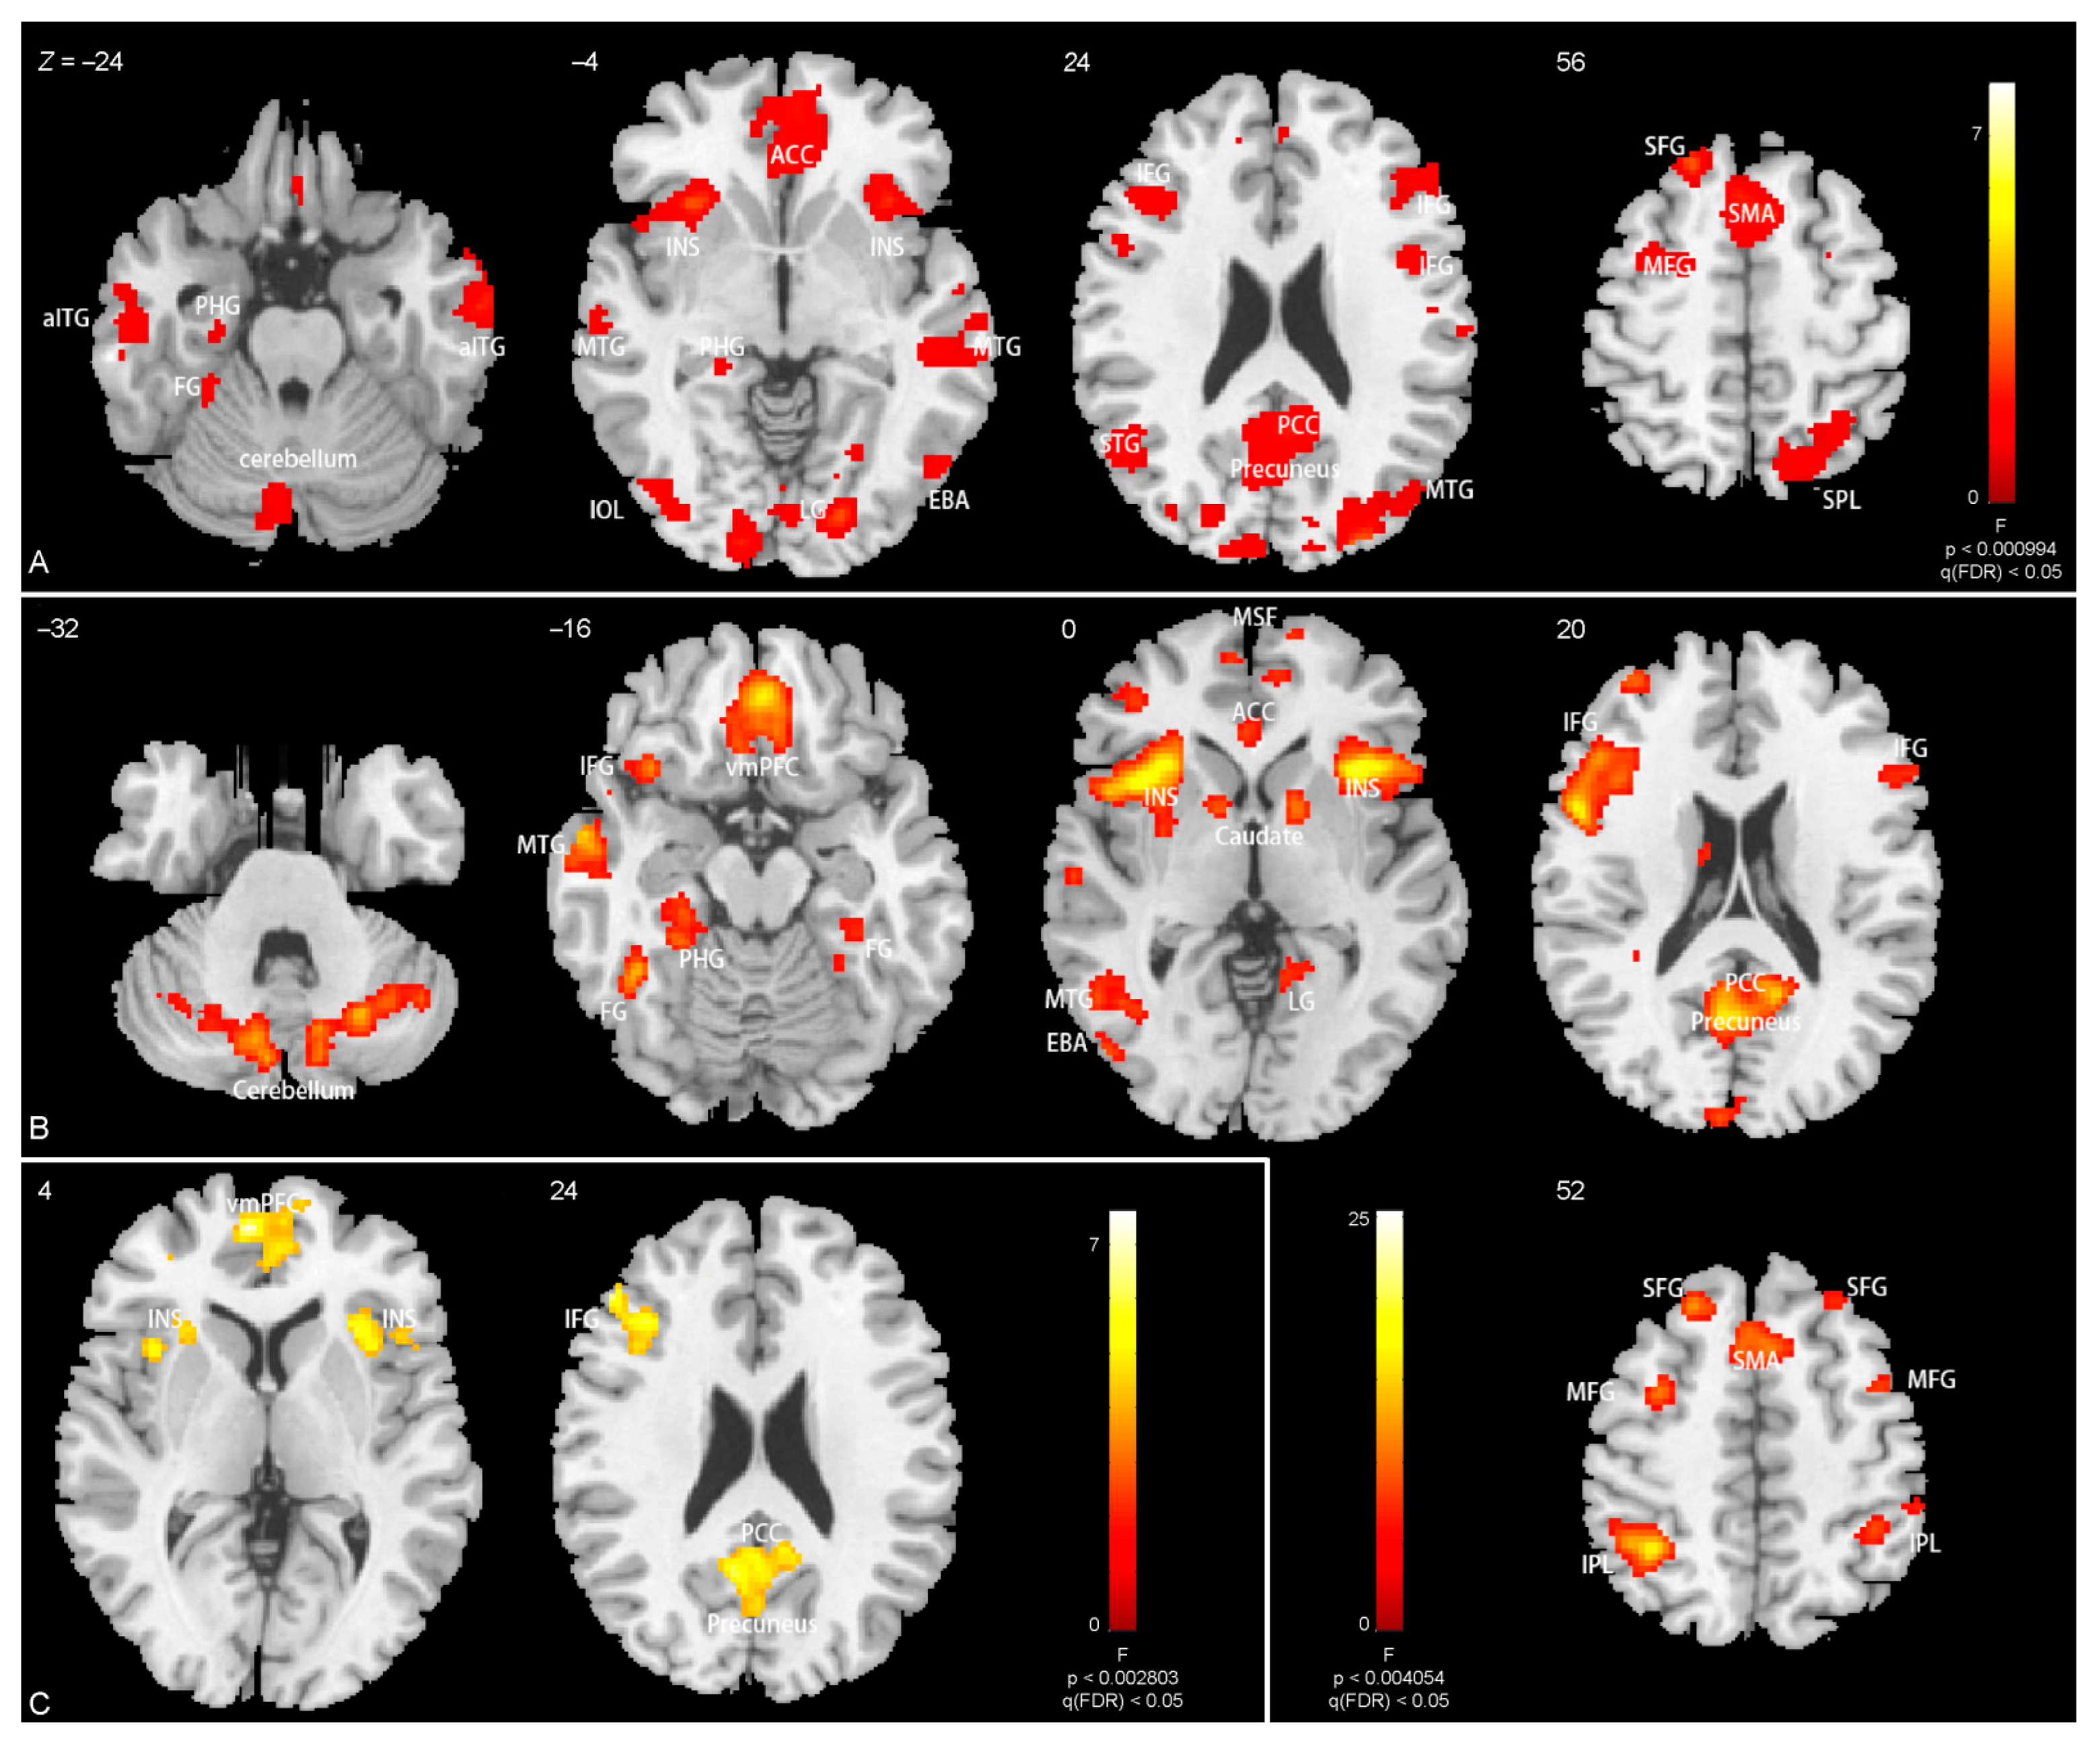

3.3. Brain Activations

| Emotion × body interactions | ||||||

| Ventromedial prefrontal gyrus | −8 | 56 | 2 | 7.6 | 1.5 × 10−5 | 143 |

| R anterior insula | 30 | 20 | 0 | 7.5 | 0.0021 | 62 |

| L precuneus | −8 | −56 | 28 | 6.9 | 1.2 × 10−4 | 103 |

| Inferior frontal gyrus | −50 | 36 | 24 | 6.5 | 6.4 × 10−4 | 426 |

| Main effect of expression | ||||||

| L cerebellum | −12 | −74 | −34 | 14.5 | 0.0033 | 104 |

| R cerebellum | 24 | −66 | −30 | 13.5 | 4.7 × 10−4 | 150 |

| L fusiform gyrus | −30 | −36 | −20 | 13.4 | 0.031 | 58 |

| L middle temporal gyrus | −60 | −4 | −18 | 18.0 | 0.0019 | 118 |

| Ventromedial prefrontal gyrus | 0 | 44 | −16 | 16.4 | 2.7 × 10−7 | 380 |

| L inferior frontal gyrus, L insula | −30 | 22 | −4 | 25.2 | 8.3 × 10−15 | 1115 |

| R inferior frontal gyrus, L insula | 34 | 20 | 2 | 19.5 | 1.4 × 10−8 | 489 |

| R caudate | 12 | 10 | 6 | 11.8 | 0.050 | 50 |

| L(R) posterior cingulate, precuneus | −6 | −60 | 20 | 16.1 | 4.0 × 10−10 | 633 |

| L(R) medial frontal gyrus | 6 | 52 | 10 | 16.6 | 7.5 × 10−5 | 205 |

| L inferior parietal lobule | −38 | −50 | 54 | 16.5 | 1.3 × 10−5 | 257 |

| L middle frontal gyrus | −24 | 30 | 48 | 15.0 | 0.0038 | 99 |

| L(R) supplementary motor area | −4 | 22 | 48 | 11.3 | 0.0018 | 122 |

| Main effect of body | ||||||

| R anterior inferior temporal gyrus | 60 | −10 | −24 | 11.0 | 1.7 × 10−4 | 202 |

| L anterior inferior temporal gyrus | −62 | −14 | −18 | 9.0 | 0.0032 | 118 |

| L middle occipital lobe (covering L EBA, L FBA gyrus, cerebellum) | −42 | −82 | 4 | 14.9 | 7.1 × 10−23 | 2311 |

| R middle occipital lobe (covering R EBA, R FBA gyrus, cerebellum) | 14 | −100 | 12 | 40.0 | 5.7 × 10−19 | 1732 |

| L(R) medial frontal gyrus and anterior cingulate | −4 | 44 | −20 | 11.4 | 1.3 × 10−14 | 1160 |

| L insula, L inferior frontal gyrus | −30 | 22 | −2 | 15.9 | 3.3 × 10−6 | 332 |

| R insula, R inferior frontal gyrus | 32 | 22 | 2 | 16.9 | 4.3 × 10−5 | 247 |

| Precuneus, posterior cingulate | −2 | −22 | 40 | 13.5 | 1.5 × 10−16 | 1405 |

| L inferior frontal gyrus | −42 | 28 | 26 | 9.2 | 0.0083 | 92 |

| L angular | −46 | −68 | 46 | 11.3 | 1.7 × 10−4 | 197 |

| R inferior frontal gyrus | 46 | 4 | 28 | 9.5 | 0.0039 | 112 |

| L superior parietal lobule | 18 | −68 | 50 | 11.5 | 1.7 × 10−4 | 198 |

| L(R) supplementary motor area | −4 | 20 | 50 | 17.3 | 6.8 × 10−10 | 654 |

| L superior frontal gyrus | −16 | 46 | 40 | 8.3 | 0.0083 | 93 |

| L superior frontal gyrus | −20 | 32 | 54 | 14.5 | 0.0012 | 144 |